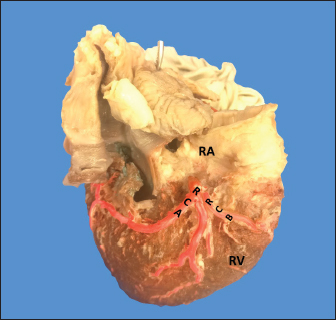

The SANB presented a dual origin (RCA and LCA) in 46.4% of the cases and a single origin from the LCA in 15 (53.6%) specimens. When the SANB branched from the left coronary circulation, it originated from the LCXB in 23 (82.1%) of the hearts and directly from the LCA in 17.9%. The proximal caliber of the SANB was 1.9 ± 0.5 mm. The caliber of the SANB that originated from the LCA was 2.2 ± 0.4 mm and the caliber when it originated from the RCA was 1.5 ± 0.3 mm, being statistically significant (p < 0.001). The distance to the origin of the SANB when it was a branch of the LCA was 16.9 ± 8.2 mm and when it originated from the RCA it was 17.8 ± 9.4 mm (Fig. 4).

Fig. 4. Anterosuperior view of the heart. Origin of the SANB from the LCXB (a); dual origin of the SANB (b). (RA): Right atrium; (RV): Right ventricle; (LA): Left atrium; (LV): Left ventricle; (RCA): Right coronary artery; (RCB): Right conus branch; (PIB): Paraconal interventricular branch; (LCXB): Left circumflex branch; (*): LCA; (LAVB): First left anterior ventricular branch; (PA): Pulmonary artery; (AA): Aorta artery.